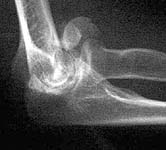

Images are of 59 yo female with low, comminuted distal humerus fx with fragments free posteriorly, high degree of comminution laterally plus involvement of the medial condyle.

at 59 years old, i would opt for ORIF. i would use a posterior approach with olecranon osteotomy - double plating with plates perpendicular to each other - with the goal being anatomic restoration and stable fixation for early motion to minimize stiffness. It is hard to say more since I would want to see more of the radiographic studies for preoperative planning. (ie, at least the AP x-ray, and probably at least a few more of the CT images). From what I can see, i think the main fragments are large enough for stable fixation. If not, the fixation might need supplementation with one of the hinged external fixators. i think the large anterior fragment seen on the lateral view is the capitellum and it would have to be retrieved. i think it would be possible with the posterior approach, but that is where access to more imaging would be helpful.